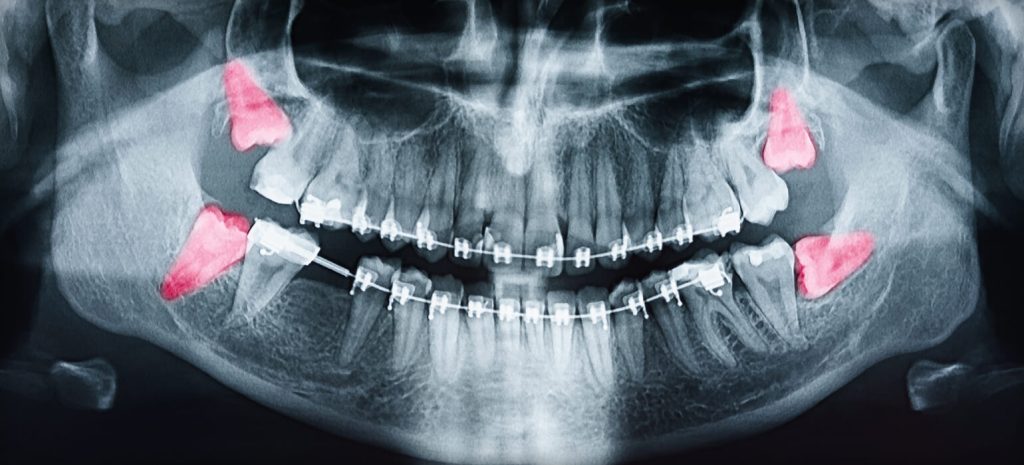

Les dents de sagesse, ou troisièmes molaires, apparaissent généralement entre 17 et 25 ans. Dans certains cas, elles poussent sans problème, mais souvent, elles n’ont pas suffisamment d’espace pour émerger correctement. Cela peut entraîner des douleurs, des infections, un déplacement des autres dents, ou des kystes.

Chez Soins dentaires Stephan, nous évaluons la position et l’état de vos dents de sagesse à l’aide d’examens cliniques et radiographiques pour déterminer si leur extraction est nécessaire.